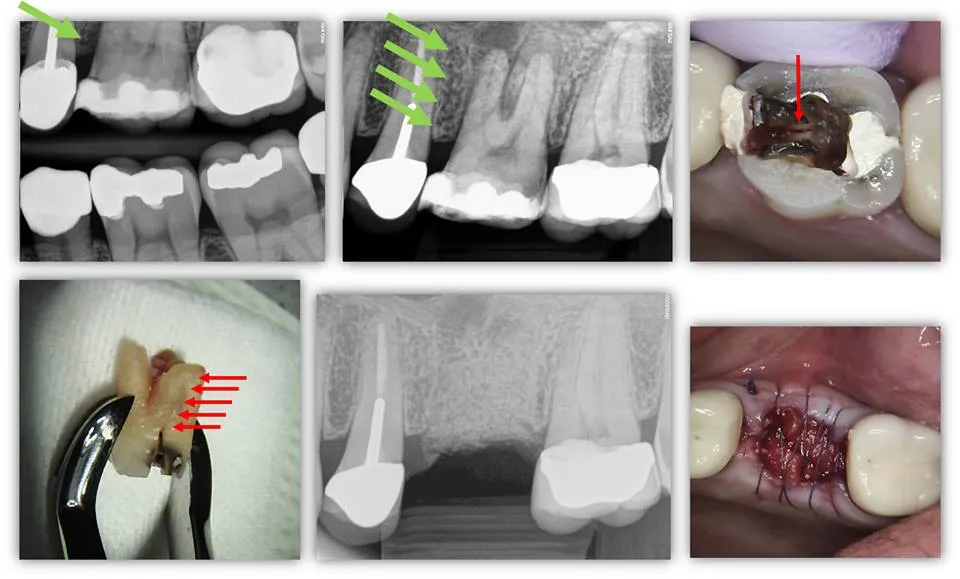

PROPER DIAGNOSIS OF NON-RESTORABLE TOOTH FRACTURES: This patient presents to our office with attempted excavation of an existing restoration and to evaluate the extent of a fracture in the crown (the patient had an MOD composite restoration). It was known by the restorative dentist that the tooth was necrotic (Note MB root lesion). For whatever reason, the dentist decided at this point to temporize and send to us for case management. BEFORE clinical exam and considering CBCT, we had noted several key factors in the PA and BW radiographs; the most important facto was the presence of bone loss on the mesial aspect of the tooth as evidenced by the green arrows. This would be highly suggestive that the crown fracture traverses below both CEJ and level of the alveolar crest. This is because bacteria populates into the fracture causing a localized inflammatory response and resultant bone loss (green arrows). Interestingly, this case didn’t probe even under pressure (this is possibly because the placement of the probe wasn’t at the exact angle of the bony defect). In any case, the patient was informed that this was not a restorable situation and it was decided that a dental implant would be done (the adjacent crowns were deemed adequate and there was no plan for replacement despite a slight distal overcontour of #14). For the sake of exercise and curiosity, the tooth was endodontically accessed to reveal a fracture that traverses the pulp chamber floor. Upon extraction, the root fracture spanned the entire length of the MB root (red arrows). The tooth was extracted and grafted for future dental implant placement. To all my endodontist colleagues out there, who would have taken a CBCT on this case for the purpose of pre-operative diagnosis? Although we will eventually be taking a CBCT on this particular patient in preparation for the dental implant, we did not take one for diagnosis and planning for extraction/site preservation.